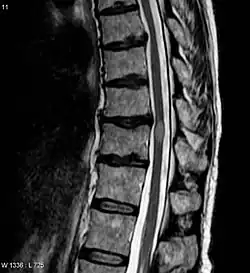

Das MRT 3 Monate nach der akuten Phase zeigt die Schädigung durch Transverse Myelitis. Die Läsion ist die hellere ovale Form in der Mitte rechts.